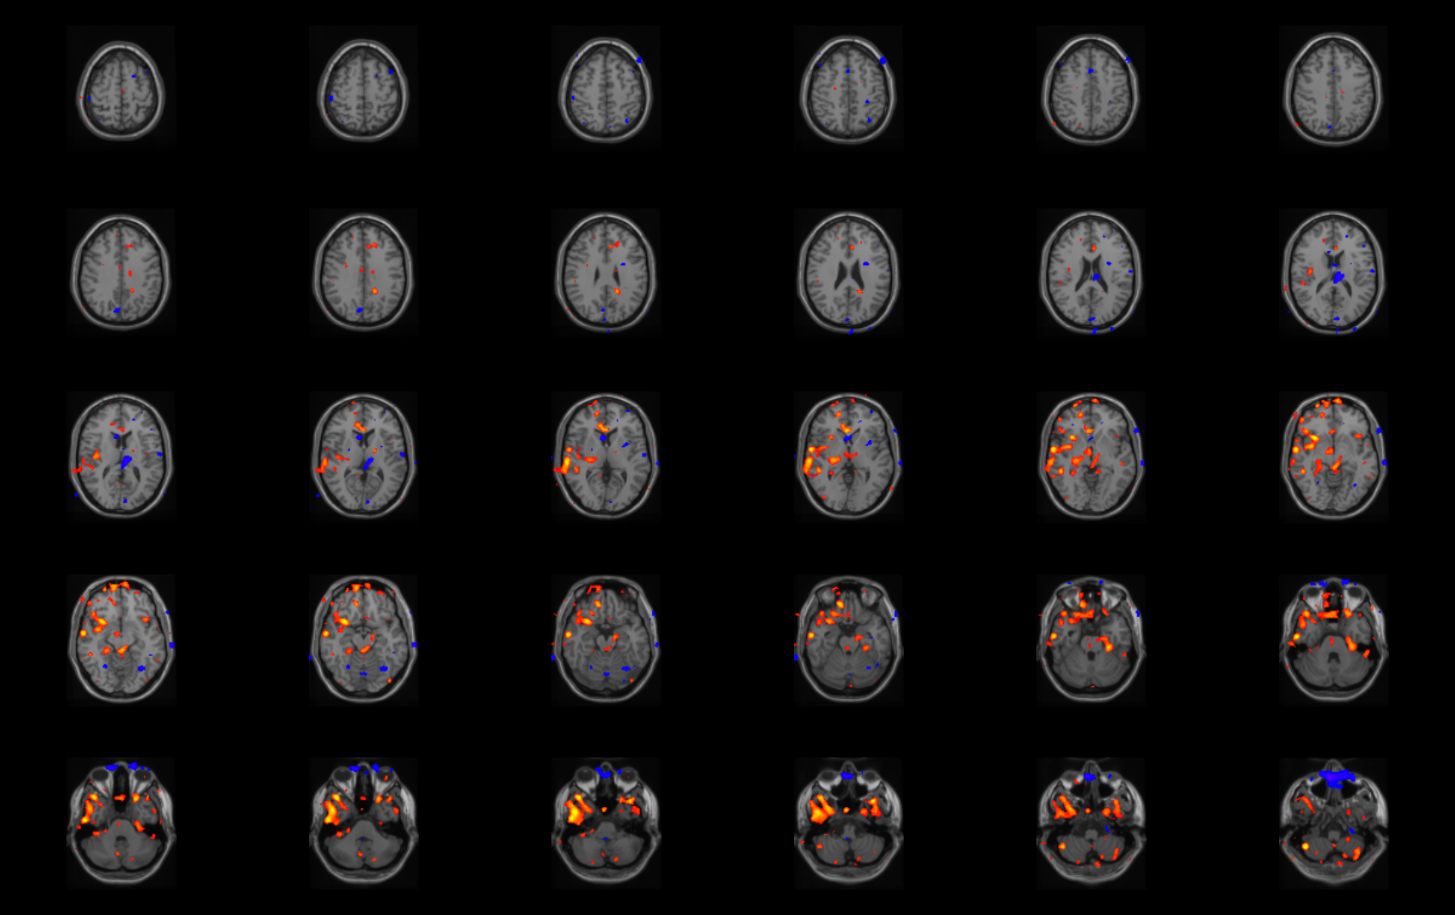

Results are shown here for ISAS analysis and RView analysis of a sample patient, as described in Instructions. This is Patient #2 from (McNally et al., 2005). The results you obtain running ISAS on the sample patient should be identical to the results displayed on this page.

ANS: All clusters displayed in Hyperperfusion and Hypoperfusion windows should be the same as shown here, and the statistics tables should be the same as shown here, with all the same clusters listed at the same significance levels, k values, and locations. Values may be off by a very small amount (less than ~5 voxels) in the table, but if the analysis was implemented correctly, then all the same clusters should be listed, and should appear identical to the coronal slices shown here.

Hyperperfusion (A) and Hypoperfusion (B) windows

Coronal Slices on Template Brain

Subtraction Processing Results for Patient#2